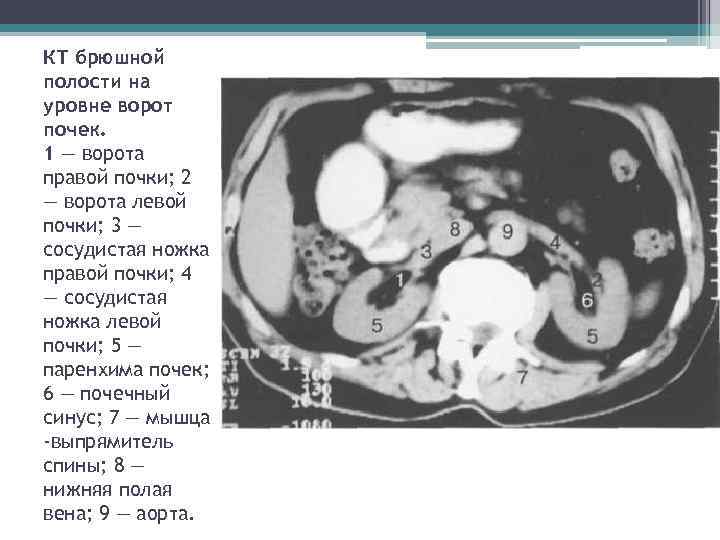

КТ брюшной полости на уровне ворот почек. 1 — ворота правой почки; 2 — ворота левой почки; 3 — сосудистая ножка правой почки; 4 — сосудистая ножка левой почки; 5 — паренхима почек; 6 — почечный синус; 7 — мышца -выпрямитель спины; 8 — нижняя полая вена; 9 — аорта.